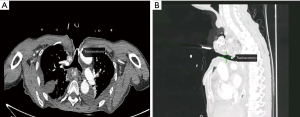

One month later, the patient was readmitted for preoperative evaluation. After neoadjuvant chemotherapy, CT revealed the location of the lesion showed a chemotherapy-induced change. Multiple air spaces were visible at the primary lesion site, and there was no obvious tumor regression (Figure 1). Esophagoscopy suggested chemotherapy-induced changes at 15 to 20 cm from the incisors, and a neoplasm with ulcers was still visible. A rupture was suspected at 20 cm from the incisors, with occasionally emerging bubbles, suggesting a possible esophageal fistula (Figure 2). Tracheoscopy revealed that the mucosa of the tracheal membrane about 5 cm above the tracheal carina was significantly swollen, and the nearby lumen was narrow (Figure 3).